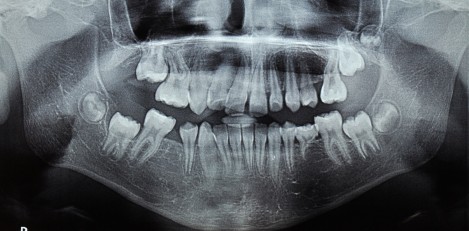

Arrested-eruption-of-first-permanent-molar

Arrested eruption of first permanent molar – frequency, clinical problems and analysis

Пробива на зъбите е естествен процес, при който формираният зъбен зародиш се доразвива и придвижва към своята позиция в челюстта до функционалното му положение в устната кухина и влизане в контакт с неговия антагонист.